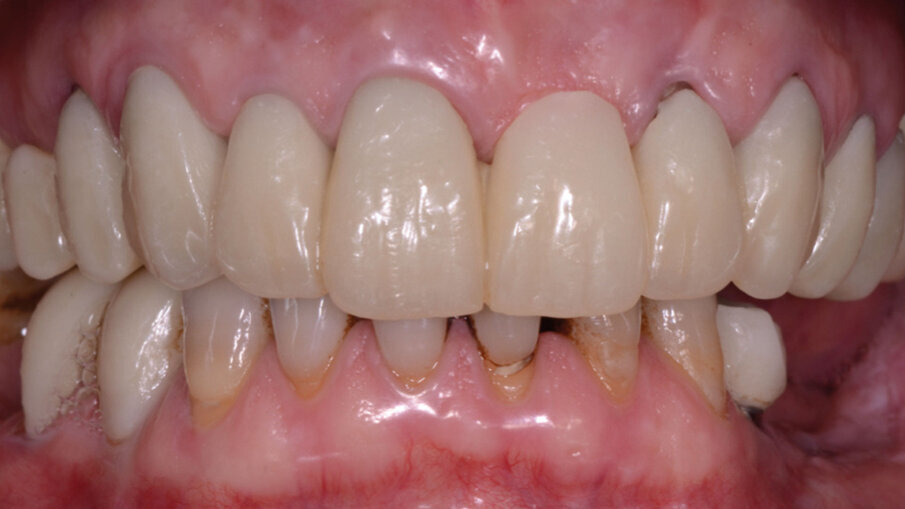

Prese le impronte definitive si passa alla prova struttura e biscotto. Successivamente alla consegna dei manufatti protesici in zirconia stratificata (Fig. 10). La paziente è stata inserita in un sistema di recall periodici gestiti dal gestionale Alfa docks che permette di interagire ergonomicamente tra gli operatori e le esigenze temporali della paziente. La gestione interdisciplinare tra gli operatori e la paziente attiva con le terapie di igiene domiciliare e i follow-up per la terapia di mantenimento hanno permesso la durata del risultato ottenuto in questi primi 5 anni (Fig. 11). L’ausilio dell’ozonoterapia domiciliare con olio di oliva ozonizzato, ha permesso il controllo del biofilm batterico mantenendo la luminosità del sorriso. La paziente è soddisfatta di aver migliorato l’estetica del suo sorriso, importante per la sua vita di relazione.